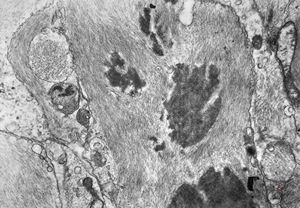

F,49y. | purulent meningitis- meningococcal v.s.

F,49y. | purulent meningitis- meningococcal v.s.

F,49y. | purulent meningitis- meningococcal v.s.